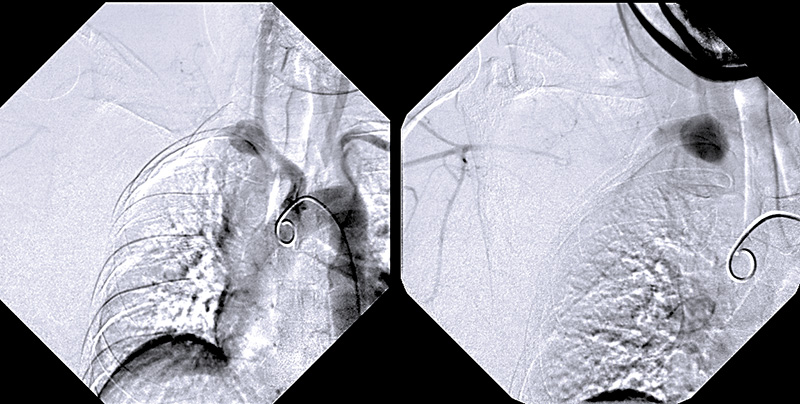

Figur 1. Angiografibilder som visar hur ett pseudoaneurysm, sekundärt till en artärruptur, fyller sig i början av arteria subclavia (t v). Senare fyller sig arteria axillaris via kollateraler, medan kontrasten dröjer kvar i pseudoaneurysmet (t h).

Det kliniska beslutsfattandet kring patienterna är ofta svårt. Även om konservativ behandling ofta är det bästa alternativet kan det straffa sig att inte vara tillräckligt aktiv. Vi upplevde detta starkt för några år sedan när vi behandlade en tidigare odiagnostiserad kvinna som drabbats av ruptur av arteria subclavia i samband med sin första förlossning (Figur 1). Medan vi trycksänkte patienten och konfererade om vi skulle behandla henne endovaskulärt eller öppet avled hon plötsligt då det 10 dagar gamla pseudoaneurysmet brast in i pleura [14]. Diagnosen vaskulärt Ehlers–Danlos syndrom misstänktes på kliniska grunder, men kunde ställas molekylärgenetiskt först efter denna tragiska händelse.